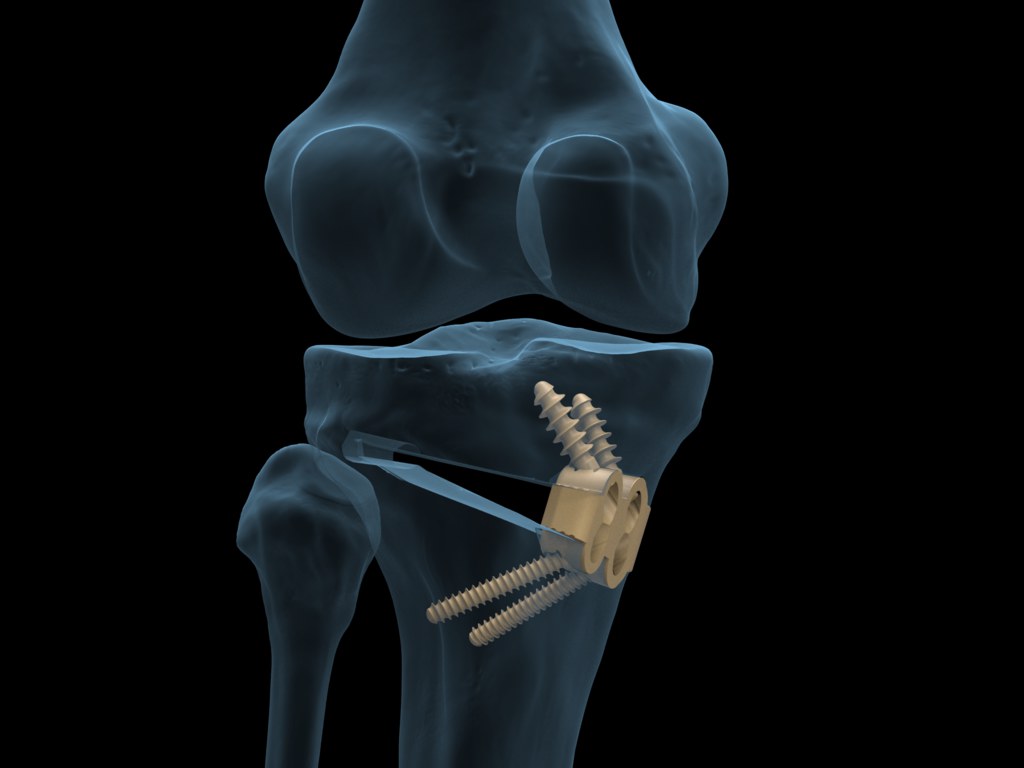

HTO

First introduced by Jackson and Waugh in 1961, high tibial osteotomy (HTO) has become popular by Conventry since 1965 as a treatment modality for medial compartment osteoarthritis of the knee with varus deformity. The goals of HTO are two fold:

1) To reduce knee pain by transferring weight-bearing loads to the relatively unaffected lateral compartment in varus knees; and

2) To delay the need for a knee replacement by slowing or stopping destruction of the medial joint compartment.

Although the employment of HTO has declined recently due to the improvement of knee arthroplasty, it is indisputable that appropriate patient selection, precise surgical planning, and various operative techniques can provide favorable treatment outcomes of HTO. The remaining areas of controversy regarding HTO include the choice of opening vs. closing wedge HTO, graft selection in opening wedge HTO, type of fixation, comparative advantages over uni-compartmental knee arthroplasty and the influence of HTO on subsequent knee arthroplasty.

Fracture of the medial or lateral tibial cortical hinge and intra-articular fracture are commonly encountered after HTO, which can disrupt stability and healing at the osteotomy site and congruence of the articular surface. In these cases, the use of locking metal plates or extra screws and metal plates can provide stale fixation for reduction of the risk of loss of correction and nonunion. The incidence of nonunion after HTO has been reported to be 0.7-4.4%. The risk factors for nonunion include large degree of correction in HTO, smoking, and insufficient fixation.